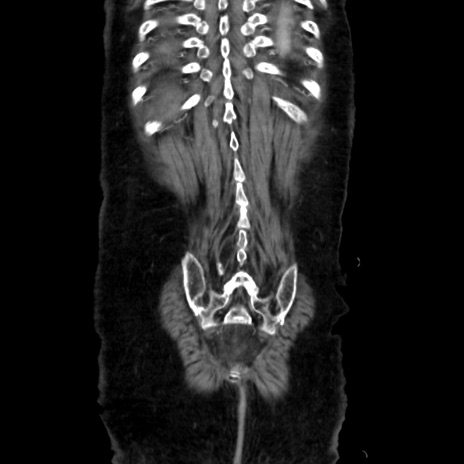

症例40(冠状断像)

矢状断像